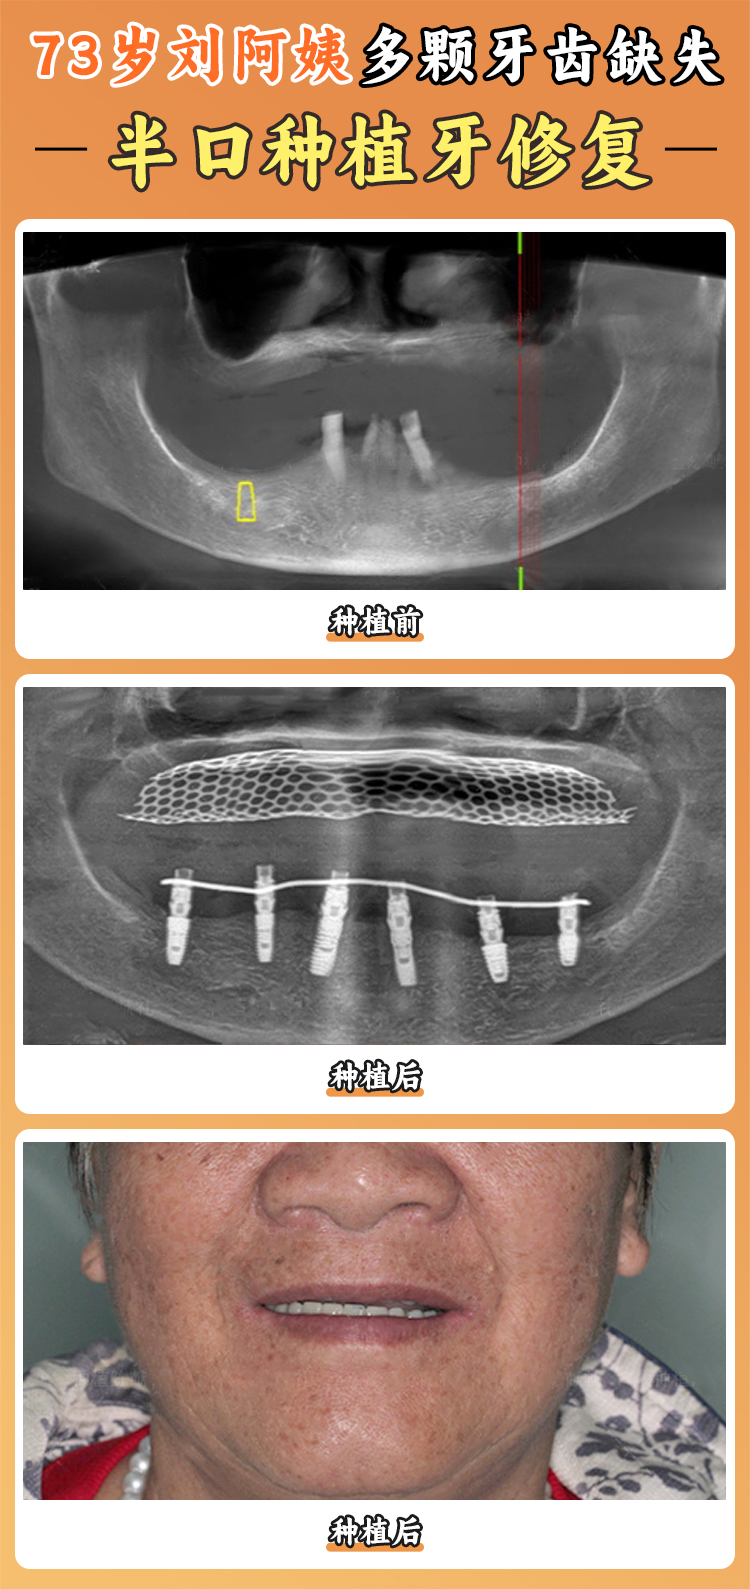

種植牙,俗稱種牙,是一種較新的成熟的口腔修復(fù)治療方法,其方法是在缺失牙的頜骨內(nèi)通過小手術(shù)植入鈦金屬的人工牙根(即種植體),使其與頜骨愈合為一體,然后在人工的牙根上鑲裝假牙(即義齒),以恢復(fù)牙列的完整性和缺失牙的功能,還你明眸皓齒。